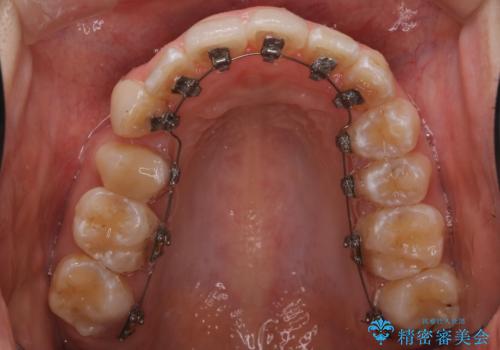

- リンガル装置

- 他院で矯正治療を受けていた患者様が、より理想的な仕上がりを求めて転院されました。主なお悩みは正中(前歯の中心)がズレていることで、歯並び全体をきれいに整えたいとのご希望でした。治療には舌側(裏側)に装置を装着するフルリンガル矯正を採用し、さらにアンカースクリューを用いて奥歯を後方へ移動(遠心移動)させることでスペースを確保し、正中を調整する計画を立てました。

矯正装置を装着し、アンカースクリューを活用しながら奥歯を少しずつ後ろへ動かし、正中を整えていきました。治療には時間がかかりましたが、計画通りに歯を移動させ、バランスの取れた歯並びへと仕上げることができました。裏側矯正のため、見た目を気にすることなく治療を進められた点も、患者様にとって大きなメリットでした。治療後は、「正中がしっかり合って、口元がスッキリした」とご満足いただきました。